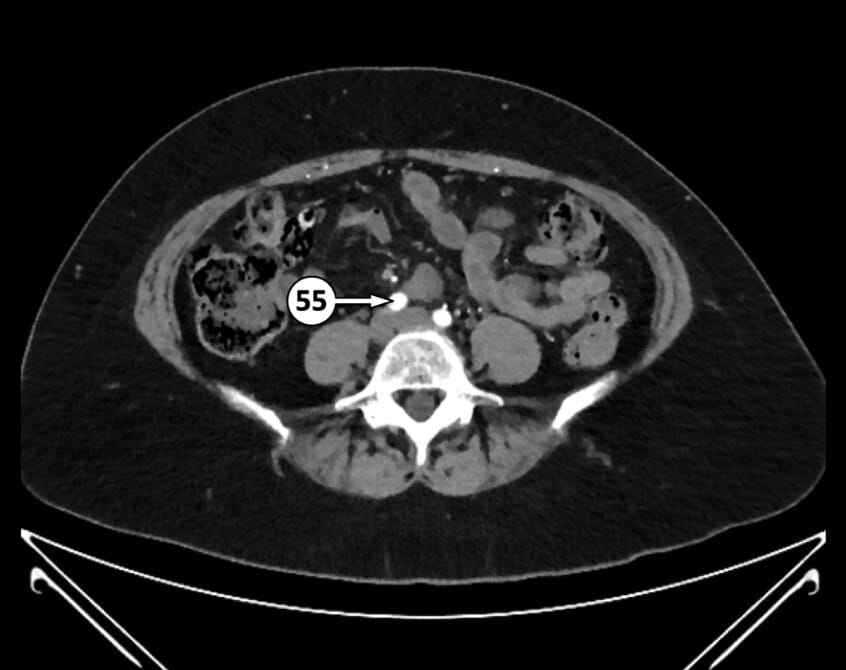

55. right common iliac artery